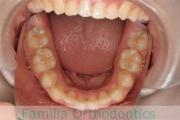

歯並びを治したいということで来院されました。下あごがやや右側に偏位して後退している、上顎前突(出っ歯)でした。上下左右から小臼歯を抜歯して、歯科矯正用アンカースクリューを併用したマルチブラケット法にて治療を行いました。約2年、24回の来院をしていただきました。

下顎の後退はいびきなどの上部気道の障害が出やすいと考えられます。